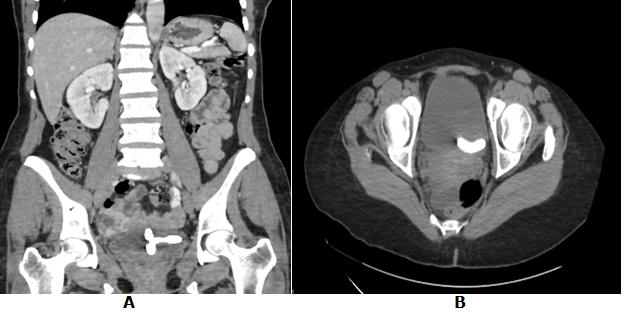

She was stable at admission, and apyretic. Physical examination found a soft abdomen with suprapubic tenderness without defense or contracture. The external urethral meatus was normal. A routine vaginal examination was normal. Cytobacteriological examination of urine (CBEU) found a positive leukocyturia (150 000/ml), microscopic hematuria (42 000/ml), and negative culture. The kidney, ureters, and bladder (KUB) x-ray revealed a T-shaped IUCD on the suprapubic region (Figure 1). Pelvic ultrasonography showed a T-shaped echogenic focus within the bladder. Computed tomography (CT) showed a hyperdense T-shaped material related to calcified IUCD (Figures 2 & 3).

Figure 1 Kidney, ureter, and bladder radiography showing a T-shaped IUCD on the suprapubic region.

Figure 2 Computed tomographic scan showing a calcified IUCD in the urinary bladder.